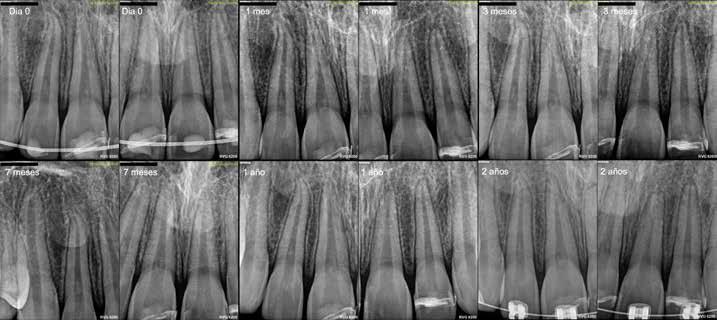

Los controles clínicos y radiográficos se realizaron a las 3 semanas (retirada de férula), 3 meses, 7 meses, 1 año y 2 años (Figuras 4z y 5). En todos los controles, los dientes mostraron respuesta normal a la prueba de sensibilidad al frío, sin molestias a la palpación ni a la percusión, y sin signos patológicos radiográficos.

En el control a los tres años post-traumatismo (Figura 6), se observó obliteración parcial del conducto radicular del 2.1, con el paciente asintomático.

Figura 5: Evolución radiográfica del caso clínico desdel traumatismo hasta los dos años de seguimiento.